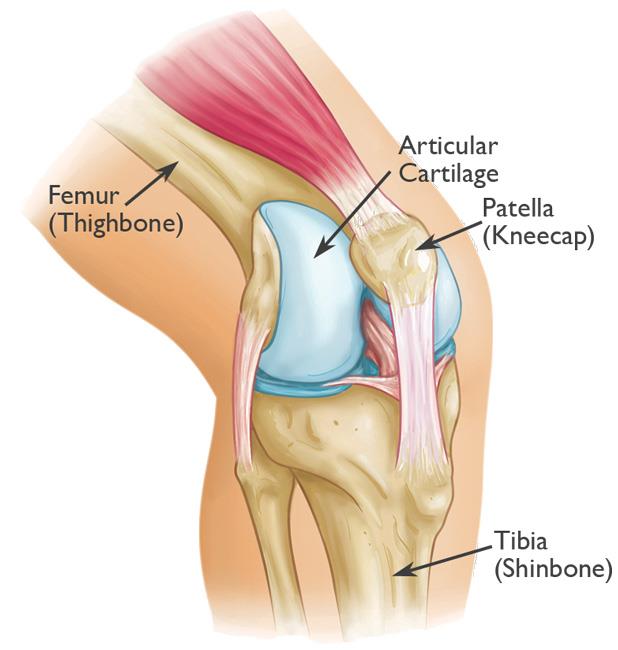

Knee Bones Anatomy Function Injuries Knee Pain Explained shop, Patellar Fractures Broken Kneecap OrthoInfo AAOS shop, Patella Kneecap Anatomy and Function shop, Knee Anatomy Arthritis health shop, The Kneecap Patella and Knee Joint Saint Luke s Health System shop, Patella Wikipedia shop, Knee Joint Function Anatomy shop, Patella the Knee Cap shop, Normal Anatomy of the Knee Joint Middletown Knee Treatment Old shop, Where or Where Has My Patella Gone Direct Orthopedic Care shop, Knee Joint Anatomy and Arthritis SHELBOURNE KNEE CENTER shop, Physiotherapy in Calgary for Knee Pain Bipartite Patella shop, Patella Anatomy function and clinical aspects Kenhub shop, Patellofemoral Pain Syndrome My Family Physio shop, Why You Have a Kneecap and How it Unleashes Your Quads shop, Physiotherapy in Calgary for Knee Pain Bipartite Patella shop, Knee Anatomy Sweep shop, Patella Kneecap Bone Xray Front Anterior Stock Illustration shop, Patella Wikipedia shop, Patella Knee cap Joint surgeon shop, Patella Fracture Broken Knee Cap Orthoriverside shop, Patellofemoral Pain Syndrome OrthoInfo AAOS shop, Knee replacement Understanding your knee shop, Is there something wrong with my kneecap Coastal Orthopedics shop, Has Anyone Dealt With a Knee Cap Bone Spur Training TrainerRoad shop, What You Need to Know About Kneecap Injuries Sports health shop, Knee Trauma Fractures of the Patella Tibial Plateau and Distal shop, Patella or kneecap bone Anatomy bones Leg muscles anatomy shop, Dislocated Kneecap Dislocated Patella for Parents Nemours shop, Kneecap Pain shop, Knee Pain Location Chart SPORT Orthopedics Dallas and Frisco shop, Knee Pain Causes Treatment shop, Why Kneecapping Your Opponent Works shop, Chondromalacia Harvard Health shop, Knee replacement Understanding your knee shop.

Knee Bones Anatomy Function Injuries Knee Pain Explained shop, Patellar Fractures Broken Kneecap OrthoInfo AAOS shop, Patella Kneecap Anatomy and Function shop, Knee Anatomy Arthritis health shop, The Kneecap Patella and Knee Joint Saint Luke s Health System shop, Patella Wikipedia shop, Knee Joint Function Anatomy shop, Patella the Knee Cap shop, Normal Anatomy of the Knee Joint Middletown Knee Treatment Old shop, Where or Where Has My Patella Gone Direct Orthopedic Care shop, Knee Joint Anatomy and Arthritis SHELBOURNE KNEE CENTER shop, Physiotherapy in Calgary for Knee Pain Bipartite Patella shop, Patella Anatomy function and clinical aspects Kenhub shop, Patellofemoral Pain Syndrome My Family Physio shop, Why You Have a Kneecap and How it Unleashes Your Quads shop, Physiotherapy in Calgary for Knee Pain Bipartite Patella shop, Knee Anatomy Sweep shop, Patella Kneecap Bone Xray Front Anterior Stock Illustration shop, Patella Wikipedia shop, Patella Knee cap Joint surgeon shop, Patella Fracture Broken Knee Cap Orthoriverside shop, Patellofemoral Pain Syndrome OrthoInfo AAOS shop, Knee replacement Understanding your knee shop, Is there something wrong with my kneecap Coastal Orthopedics shop, Has Anyone Dealt With a Knee Cap Bone Spur Training TrainerRoad shop, What You Need to Know About Kneecap Injuries Sports health shop, Knee Trauma Fractures of the Patella Tibial Plateau and Distal shop, Patella or kneecap bone Anatomy bones Leg muscles anatomy shop, Dislocated Kneecap Dislocated Patella for Parents Nemours shop, Kneecap Pain shop, Knee Pain Location Chart SPORT Orthopedics Dallas and Frisco shop, Knee Pain Causes Treatment shop, Why Kneecapping Your Opponent Works shop, Chondromalacia Harvard Health shop, Knee replacement Understanding your knee shop.